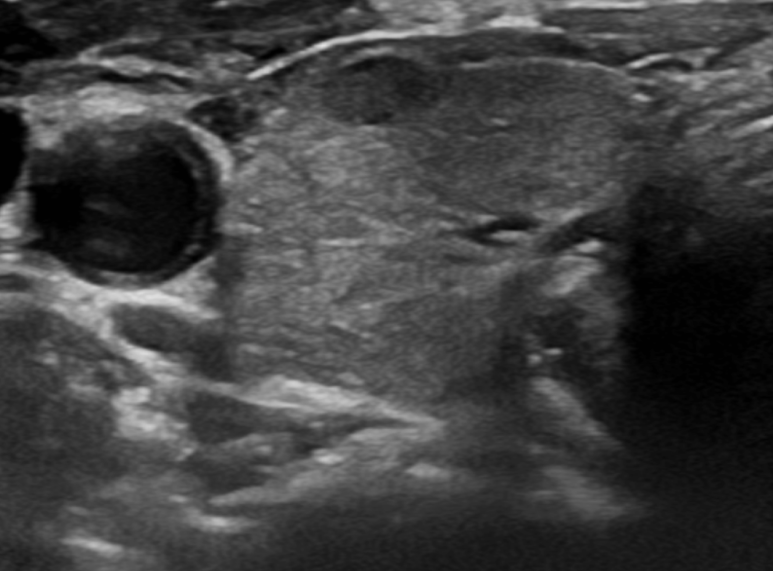

갑상선 초음파이기 때문에 갑상선 초음파를 봅니다만, 검사 전문의 진상 관련 증상이 명확하지 않았기 때문에 예상 밖의 소견이었습니다.

갑상선 표면이 고르지 못하고(Heterogenouse chogenicity) 혈관이 매우 발달되어 있습니다(hypervascularity).

초음파 소견만으로 갑상선 저하 항진인지는 정확한 구분은 어렵지만 갑상선 호르몬의 수치에 이상이 있는 것은 확실합니다.